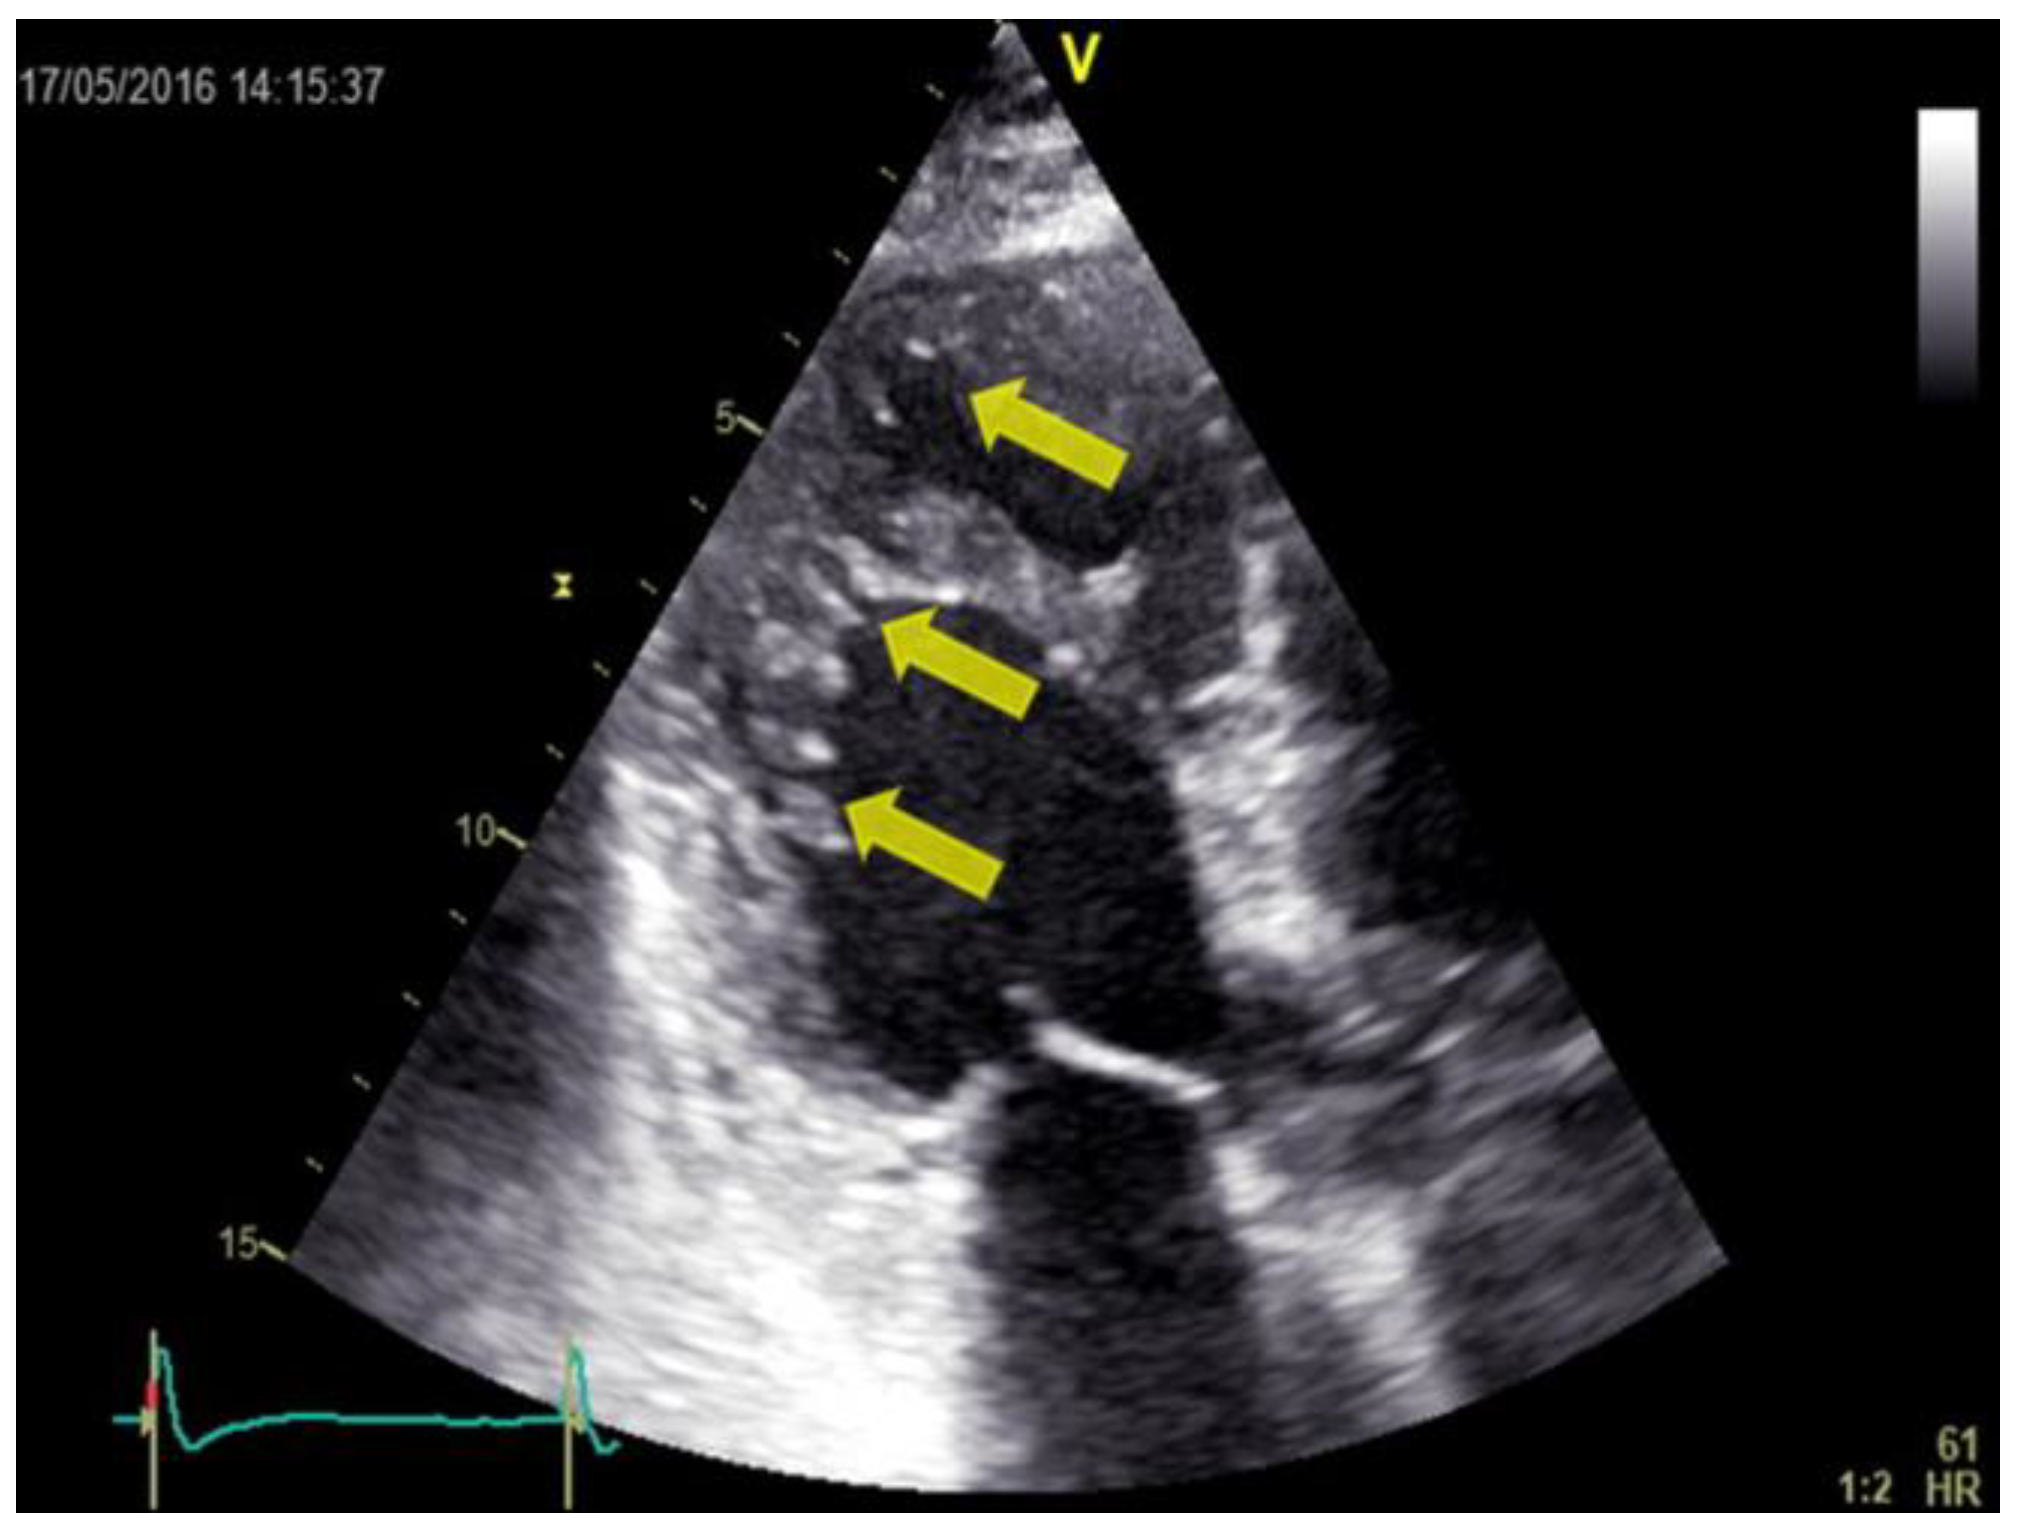

Transthoracic bidimensional echocardiography (2D- TTE) is the method of choice for diagnosing LVNC (Figure 2, Figure 3 and Figure 4). Three basic echocardiographic criteria have been proposed to define LVNC: a thick myocardium with a non-compacted layer and a compacted one; prominent trabeculations; and deep endomyocardial recesses.

Figure 3.

Bidimensional transthoracic echo- cardiography, apical 3-chamber view (the same patient as in figure 2). The hypertrabeculation can be observed in the mid and apical region of the posterior wall (yellow arrows).